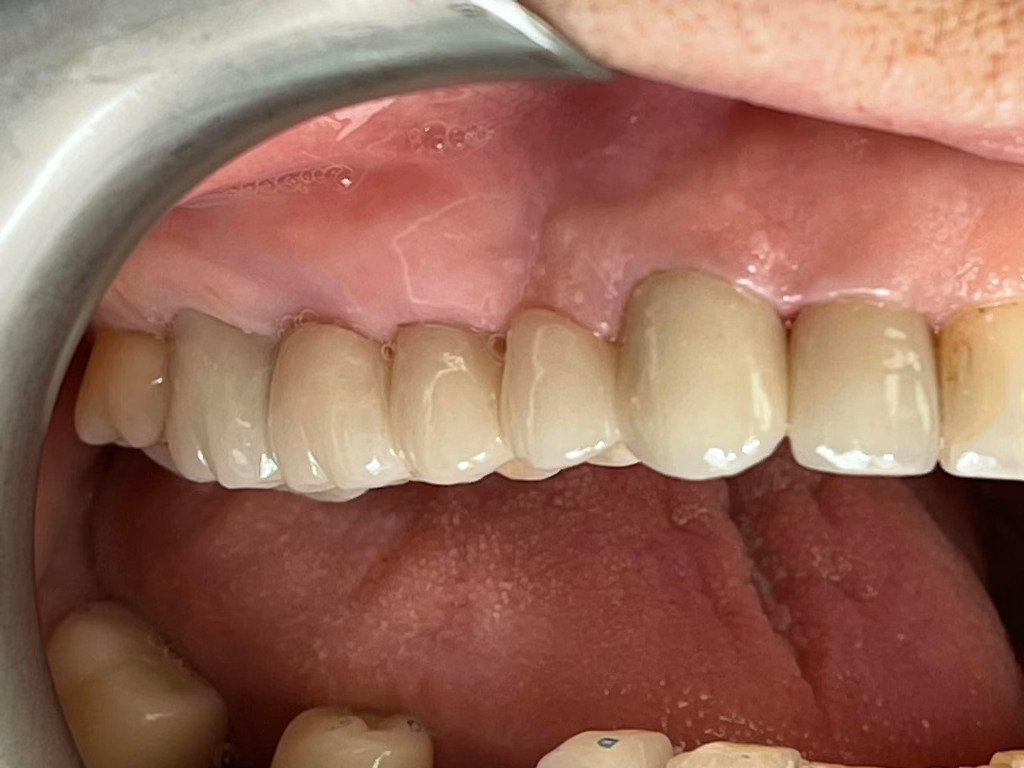

Case Study: Dental Bridges